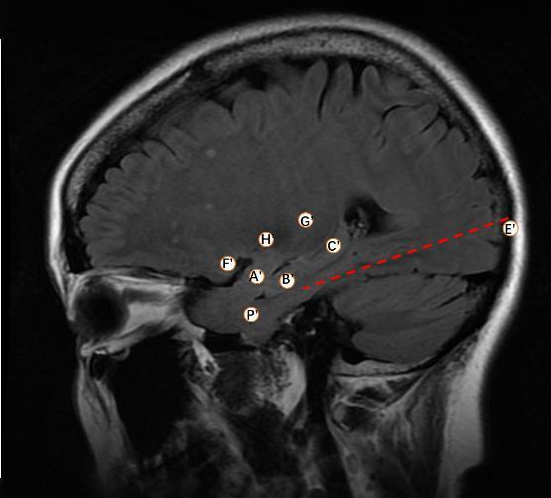

手术方案:“ROSA ONE”引导下右侧颞叶、岛叶等部位置入深部电极8根。

A’:颞中回—杏仁核

B ’:颞中回—海马头

C’:颞中回—海马尾

E’:颞下回后部—贯穿颞底—海马旁回

F’:颞极上部—岛短回腹侧

G’:颞上回—第2岛长回

H’:颞上回—第1岛长回

P’:颞极外侧—颞极内侧

图6.1 电极置入后

图6.2 电极置入后CT扫描与三维图像

图8.1 脑电监测24小时,立体脑电图间期B2-3, C1-2, E1-3放电频繁

图8.2 脑电监测24小时,1次临床癫痫发作,立体脑电图间期E1-3起始,快速向B,C电极传导

结论:ROSA ONE机器人首台电极置入成功,多根电极准确性在0.5mm左右,置入精度高,术后患者反应小,无疼痛、恶心等不适,术后24小时内扑捉到一次临床发作,发作放电位置清楚,基本确定癫痫起始点。